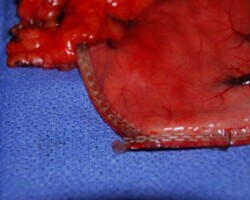

Resection of large retroperitoneal sarcoma including right and transverse colectomy and right hepatectomy